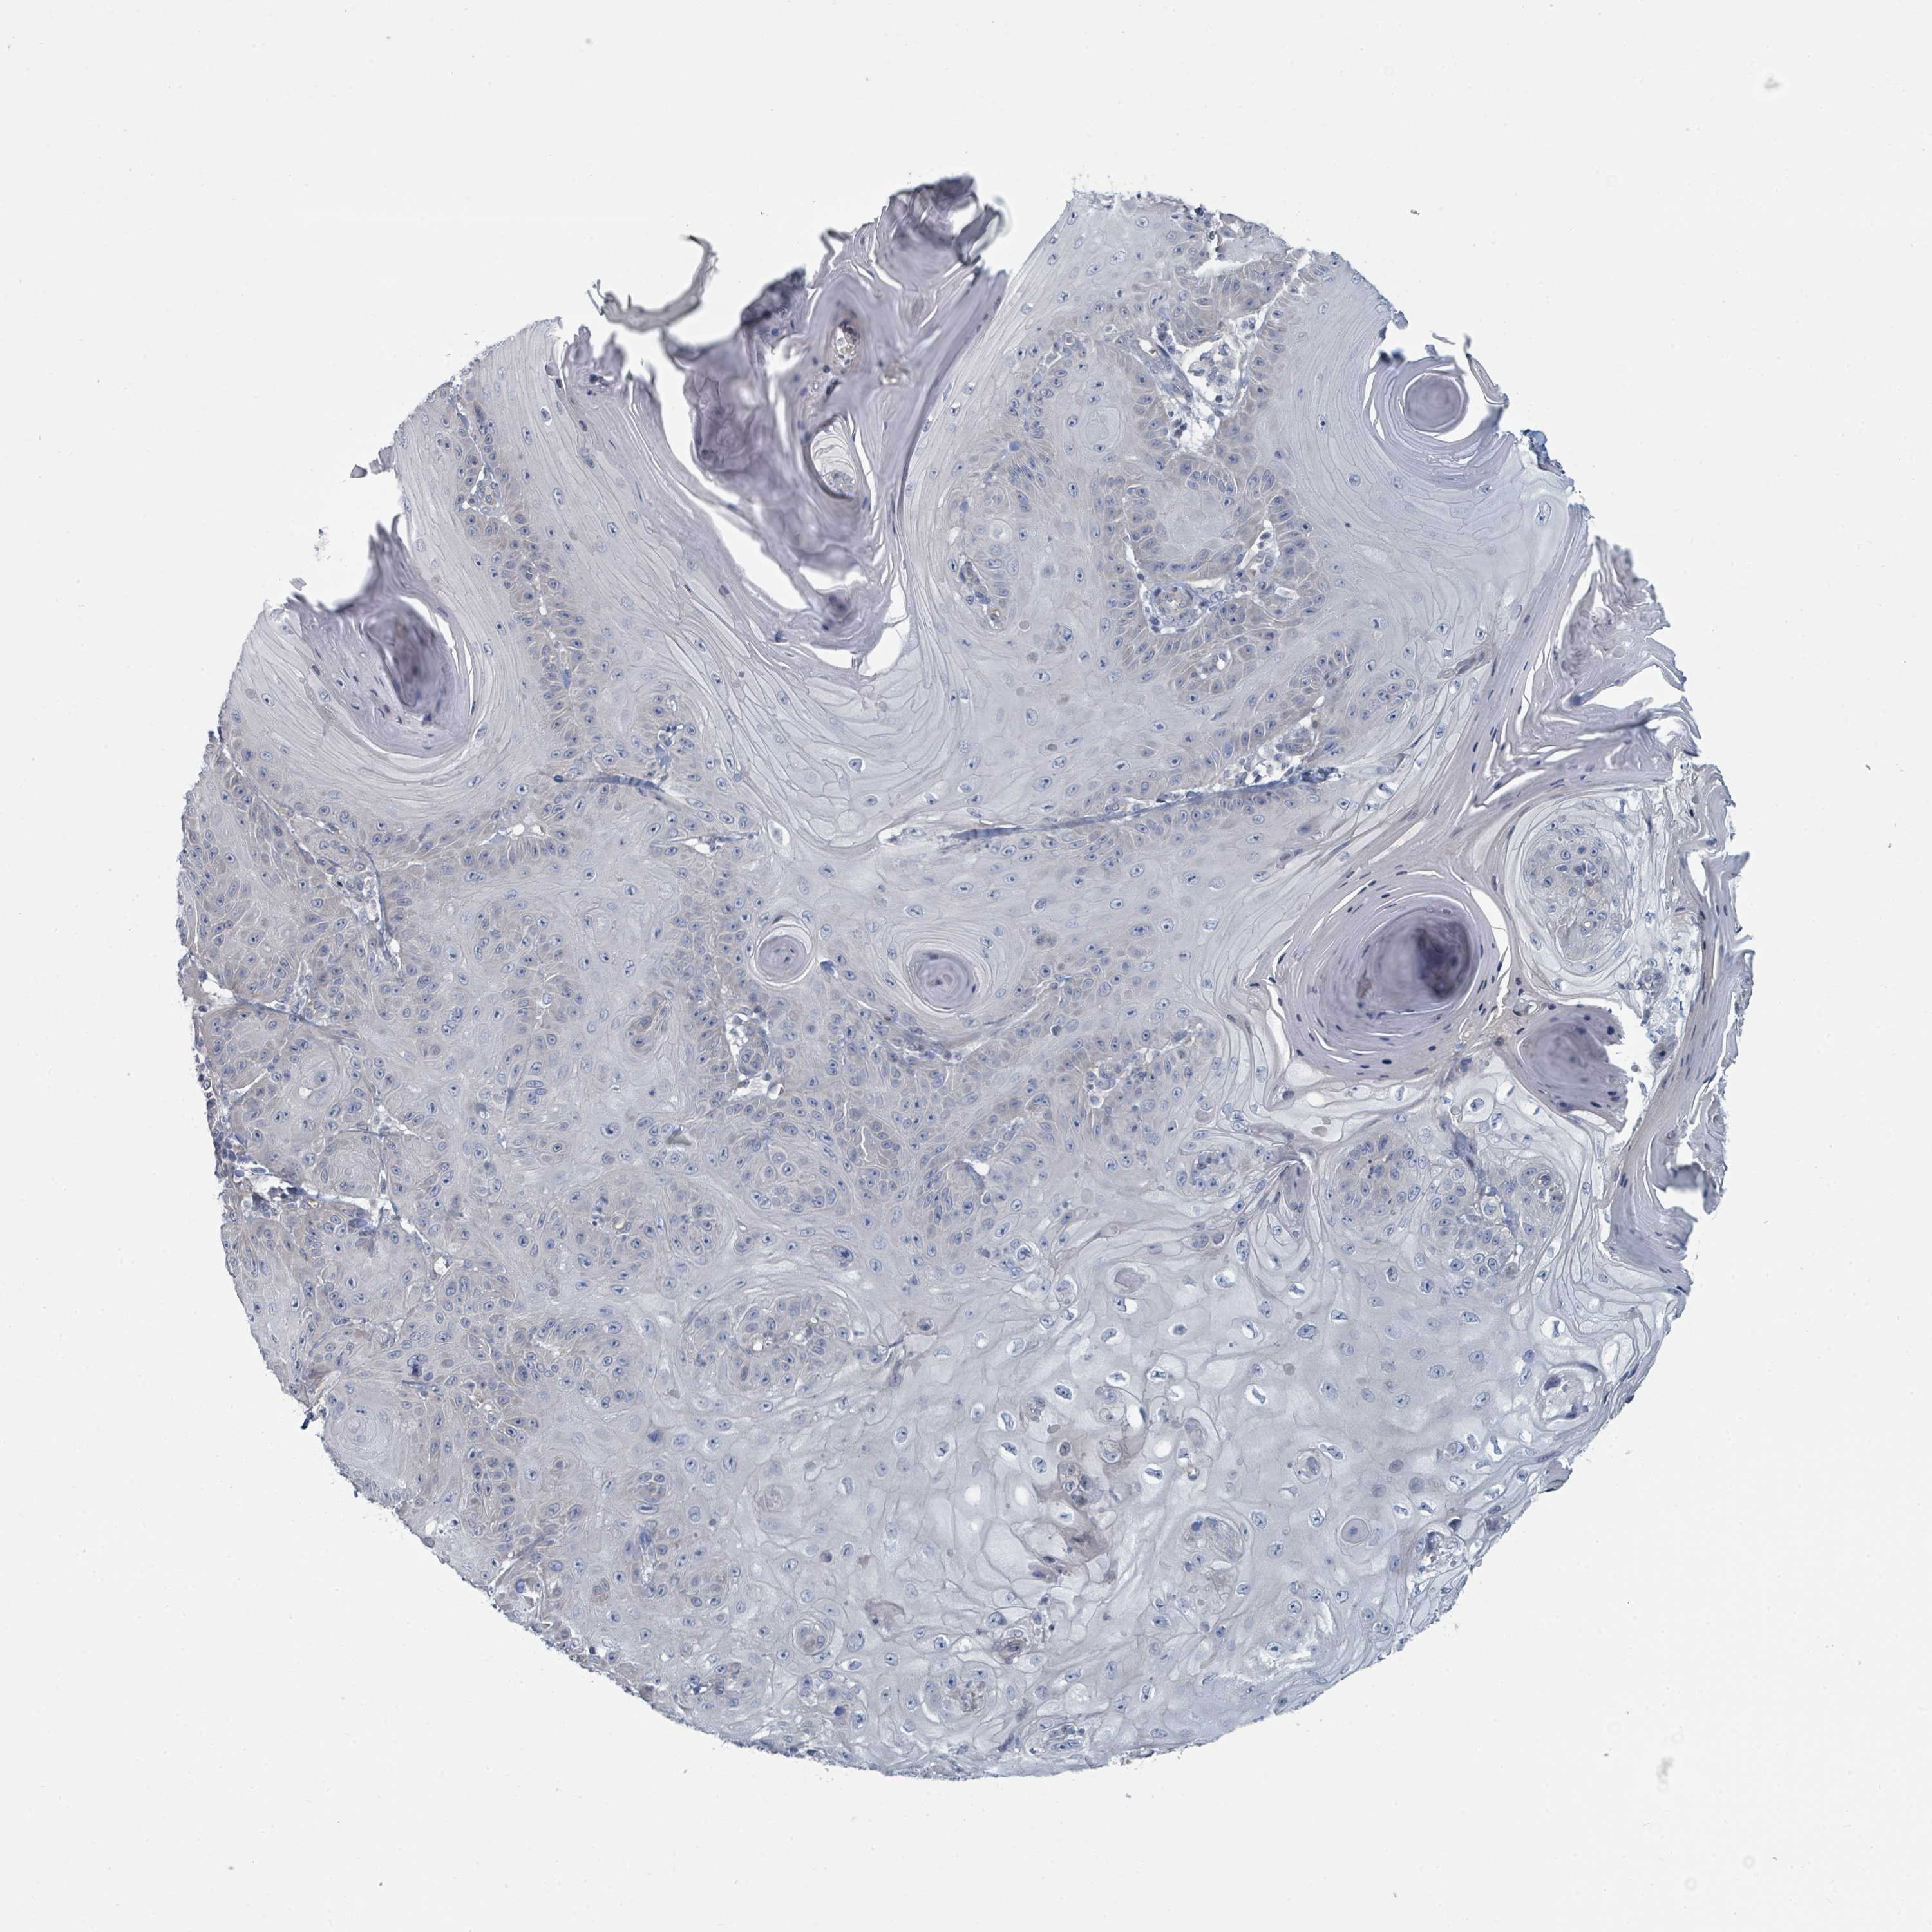

Basal cell and squamous cell cancer

SKIN CANCER - Protein expressioni

A mouse-over function shows sample information and annotation data. Click on an image to view it in a full screen mode. Samples can be filtered based on level of antibody staining by selecting one or several of the following categories: high, medium, low and not detected. The assay and annotation is described here.

Each image is clickable and will lead to virtual microscopy that enables deeper exploration of all samples and also displays staining intensity scores, fraction scores and subcellular localization as well as patient and tissue information for each sample.

Antibody HPA050821

Squamous cell carcinoma, NOS

Squamous cell carcinoma, metastatic, NOS